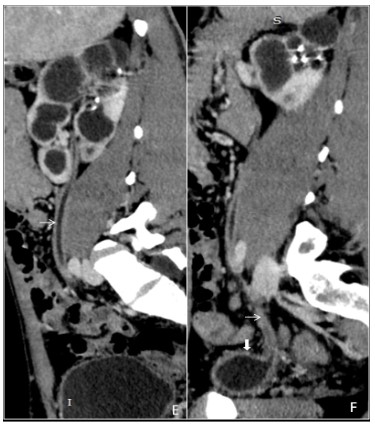

Genitourinary tuberculosis

Genitourinary tuberculosis is the second most common site of tuberculosis, caused by Mycobacterium tuberculosis, secondly to pulmonary tuberculosis. It can be divided anatomically into renal tuberculosis (renal parenchyma, calyces and renal pelvis), bladder and ureteric tuberculosis, prostatic tuberculosis, scrotal tuberculosis, tuberculous pelvic inflammatory disease (female). The kidneys are the most common site of GUTB. Clinical presentations are hematuria, frequency, urgency, dysuria with involvement of the bladder. Stricture formation is the most common complications in GUTB. Common sites of stricture formations are the neck of a calyx causing hydrocalyx, regional hydro calcinosis, pelvic-ureteric junction causing generalized dilatation of pelvicalyceal system and lower end of the ureter. Other imaging findings are parenchymal scars & irregularity of the papillary tips (motheaten calices), and small cavities in the papillae. (Figure 10A,10B,10C,10D) Sometimes fibrotic reactions may develop, leading to stenosis and strictures formations. Chronic tubercular infections in the genitourinary tract result in a ‘thimble bladder’ appearance and patulous VUJ (Figure 10E,10F). In females, pelvic tuberculosis is seen commonly in India, leading to a tubo-ovarian abscess or stricture formation (Figure 11A,11B).

Figure 10: (A) A 40 years old male patient came to our hospital three months back. After initial investigations, he was diagnosed with genito-urinary tuberculosis and started on ATT, after which the patient improved symptomatically. However, after three months, he discontinued the treatment and again presented to us with burning micturition and increased frequency of urination. The patient underwent a CT scan which is depicting a relatively enlarged left kidney with fine calcification along the calyces (black arrow) and thinning of renal parenchyma (white arrow). (B) NCCT scan at the level of the urinary bladder shows a focus of calcification in the urinary bladder near the left vesicoureteric junction (VUJ) (thick black arrow). (C) CECT scan in the axial plane at the corresponding level of the image (A) shows uneven caliectasis (black arrow). (D) Axial view from the CECT scan shows both mid parts of the ureters over the psoas muscle. There is dilatation of the left ureter and thickening and enhancement of the urothelial of the ureter (black arrow). The right ureter appears normal (white arrow). (E) A reformatted sagittal image of the venous phase from the CECT scan shows enhancing urothelial thickening of the left ureter, forming a lead pipe appearance (white arrow). (F) The reformatted sagittal image shows enhancing thickening of the urothelium of the left ureter up to the VUJ with a wide and incompetent VUJ. There is uneven dilatation of the upper calyx of the left kidney with no overlying renal cortex suggestive of phantom calyx and scar formation (white arrow). The urinary bladder has a “thimble bladder appearance” with a patulous VUJ (thick white arrow).

Figure 11: (E) A reformatted sagittal image of the venous phase from the CECT scan shows enhancing urothelial thickening of the left ureter, forming a lead pipe appearance (white arrow). (F) The reformatted sagittal image shows enhancing thickening of the urothelium of the left ureter up to the VUJ with a wide and incompetent VUJ. There is uneven dilatation of the upper calyx of the left kidney with no overlying renal cortex suggestive of phantom calyx and scar formation (white arrow). The urinary bladder has a “thimble bladder appearance” with a patulous VUJ (thick white arrow).